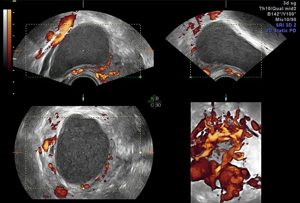

Traditional ultrasounds can miss small or deep infiltrating endometriosis. Advanced gynecological ultrasound, however, combines high-frequency probes, 3D/4D imaging, and specialized Doppler evaluation to provide detailed visualization of the uterus, ovaries, and pelvic structures.

- 3D volumetric scans for a complete anatomical overview

- Color Doppler mapping to study blood flow changes in affected tissues